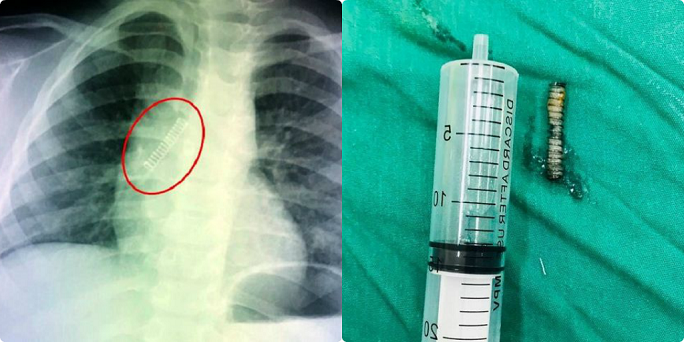

Vừa mở quả trứng đồ chơi, một cháu bé 4 tuổi ở TPHCM bất ngờ bị chiếc lò xo bắn vào miệng ho sặc sụa, tím tái phải nhập viện cấp cứu.